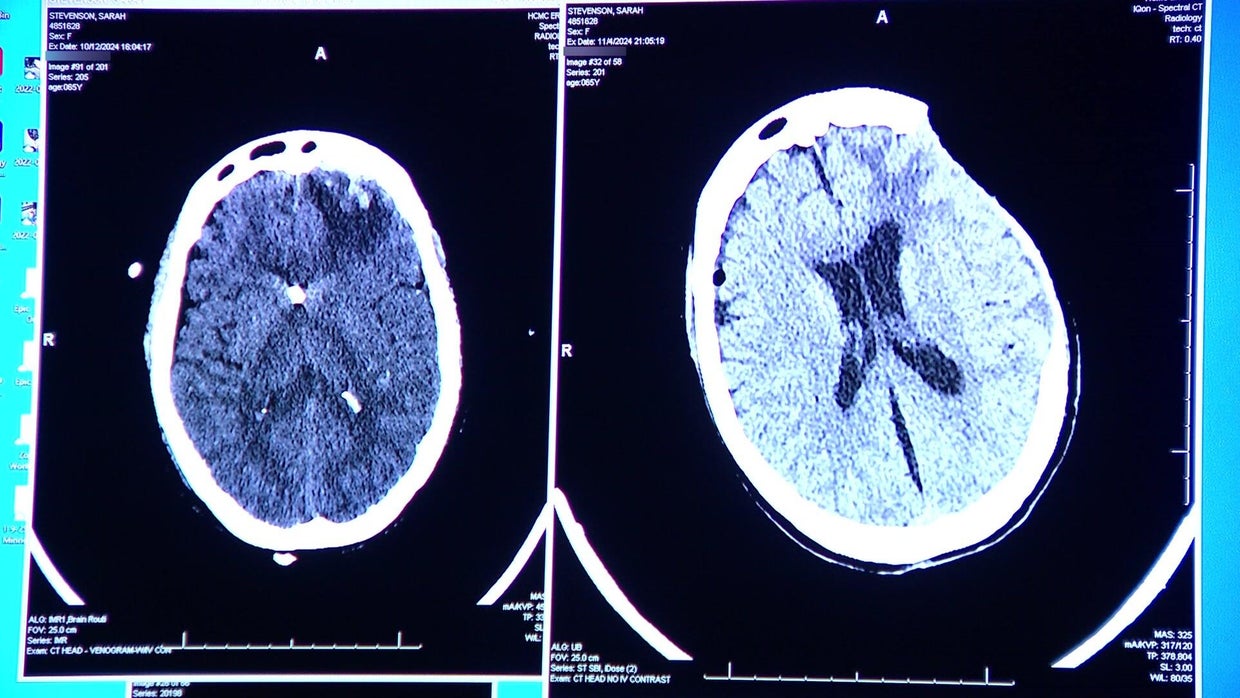

An immediate scan showed her brain was swelling fast. A normal scan should have dark spaces that have fluid, but Sarah Stevenson's showed it was fully swollen.

"That was Sarah's big problem is that her brain was starting to swell, and her brain was acting much more like a very young person. [She] had some really malignant swelling after the trauma that progressed over several days," Galicich said.